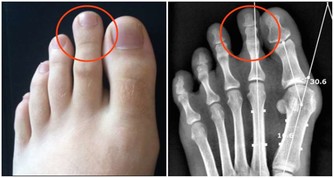

除了飲食上多吃綠色食物以外,按揉穴位也能起到養肝的效果。在這裡,不得不推薦大家按揉太衝穴。

太衝穴是人體重要穴位之一,在腳背上,第一、二蹠骨結合部之前凹陷處,它是肝經的原穴和腧穴,所以也被有的朋友稱為人體的“出氣筒”,能夠很好的調動肝經的元氣,去肝火,解肝鬱,效果實在太好了。

大家沒事的時候,例如晚上泡腳或是睡覺前,就可以按揉這個穴位,不輕不重的按揉個3、5分鐘就可以了,每次不要按時間過長,但是需要堅持下來。